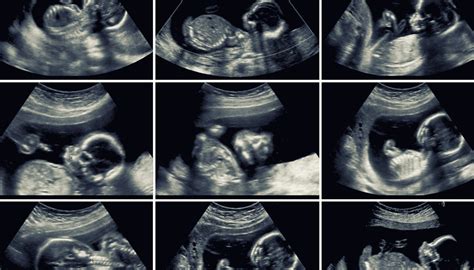

Morfologický ultrazvuk v 20. týždni tehotenstva

Dvadsiaty týždeň tehotenstva je známy tzv. morfologickým ultrazvukom. Toto vyšetrenie, označované aj ako ultrazvukový skríning v druhom trimestri alebo "veľký ultrazvuk", je považované za jedno z najdôležitejších počas tehotenstva. Vykonáva sa zvyčajne medzi 18. až 22. týždňom, pričom mnohí lekári preferujú obdobie medzi 21. až 22. týždňom pre lepšiu zrelosť plodu.

Cieľom morfologického ultrazvuku je podrobne skontrolovať celkový vývoj bábätka a odhaliť prípadné vývojové odchýlky či vrodené poruchy. Lekár detailne sleduje:

- Mozog: Jeho štruktúru a vývoj.

- Srdce: Kontroluje sa jeho štruktúra, komory a funkcia.

- Pľúca: Sleduje sa ich vývoj a pripravenosť na dýchanie.

- Obličky a močový mechúr: Kontroluje sa ich prítomnosť a funkcia.

- Tráviaci systém: Pozoruje sa žalúdok a črevá.

- Kostra: Hodnotí sa vývoj chrbtice, končatín, lebky a prstov.

- Tvárová časť: Lekár sa snaží zobraziť tvár, nos, pery a očné viečka.

- Genitálie: Pri vhodnej polohe plodu je možné určiť pohlavie dieťatka.

Okrem orgánov a kostry sa kontroluje aj:

- Pupočná šnúra: Jej správne uloženie a prietok krvi.

- Množstvo plodovej vody: Dostatočné množstvo je kľúčové pre vývoj plodu.

- Poloha a štruktúra placenty: Zabezpečuje výživu plodu.

Počas ultrazvuku sa sledujú aj chromozomálne odchýlky a výskyt prípadných porúch, ako je Downov syndróm alebo Edwardsov syndróm. Lekár tiež kontroluje deformácie alebo vývojové poruchy, napríklad tvar hlavy, veľkosť mozgu, polohu nosu, chyby chrbtice alebo vstup pupočníka do bruška.

Pre lepšiu viditeľnosť sa pri transabdominálnom ultrazvuku odporúča mať plný močový mechúr. Samotné vyšetrenie je nebolestivé a trvá zvyčajne 10 až 30 minút, v závislosti od zložitosti prípadu.